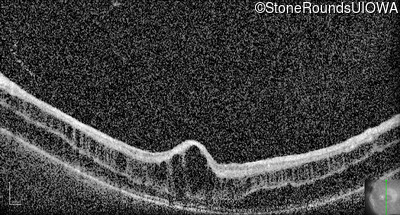

Optical Coherence Tomography - Right - 10/40

Exemplar / OCT Stack